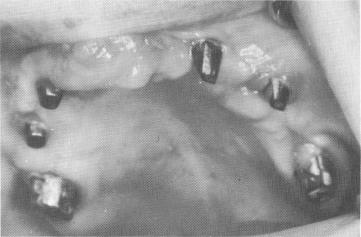

Fig. 11-132. The healed tissues 21 days postoperatively.